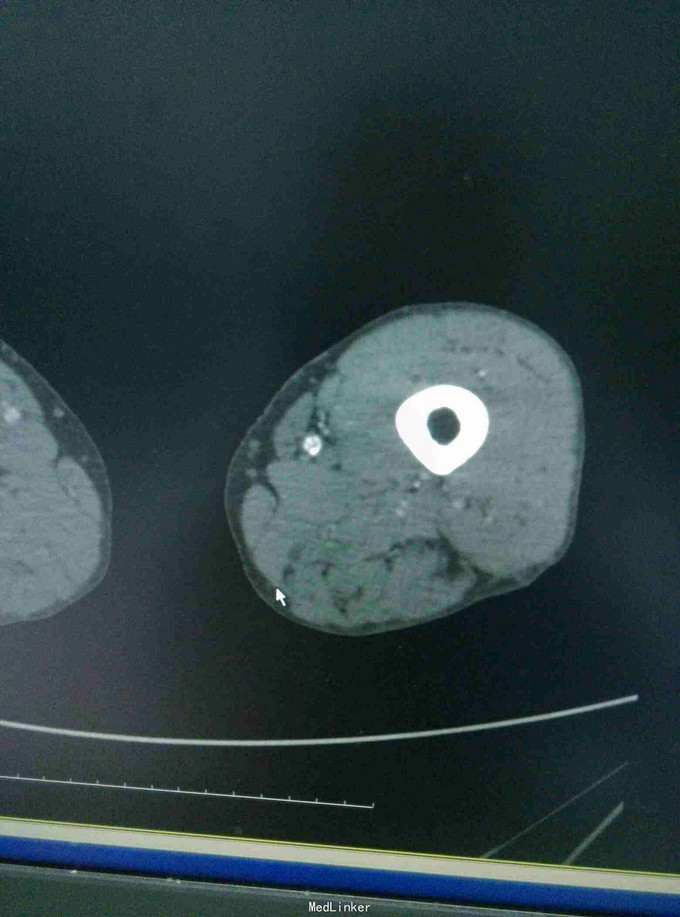

男患,74岁,间歇性跛行2年伴右足疼痛9+月,2年前无明显诱因出现间歇性跛行,行走后伴下肢远端疼痛、乏力,休息后缓解,无红肿发热及感觉异常,后行走距离渐变短,9月前加重伴远端静息痛。

左下肢皮温降低,左足背可见紫红色淤斑,左股动脉扪及微弱波动。下肢血管成像提示:双下肢动脉节段性不同程度狭窄、闭塞。